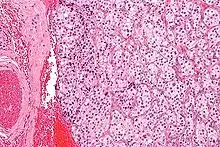

On microscopic inspection, the tumor cells are readily recognized. Individual tumor cells are polygonal to oval and are arranged in distinctive cell balls, called Zellballen.[8] These cell balls are separated by fibrovascular stroma and surrounded by sustentacular cells.

With immunohistochemistry, the chief cells located in the cell balls are positive for chromogranin, synaptophysin, neuron specific enolase, serotonin, neurofilament and Neural cell adhesion molecule; they are S-100 protein negative. The sustentacular cells are S-100 positive and focally positive for glial fibrillary acidic protein. By histochemistry, the paraganglioma cells are argyrophilic, periodic acid Schiff negative, mucicarmine negative, and argentaffin negative.

- Micrograph of a carotid body tumor